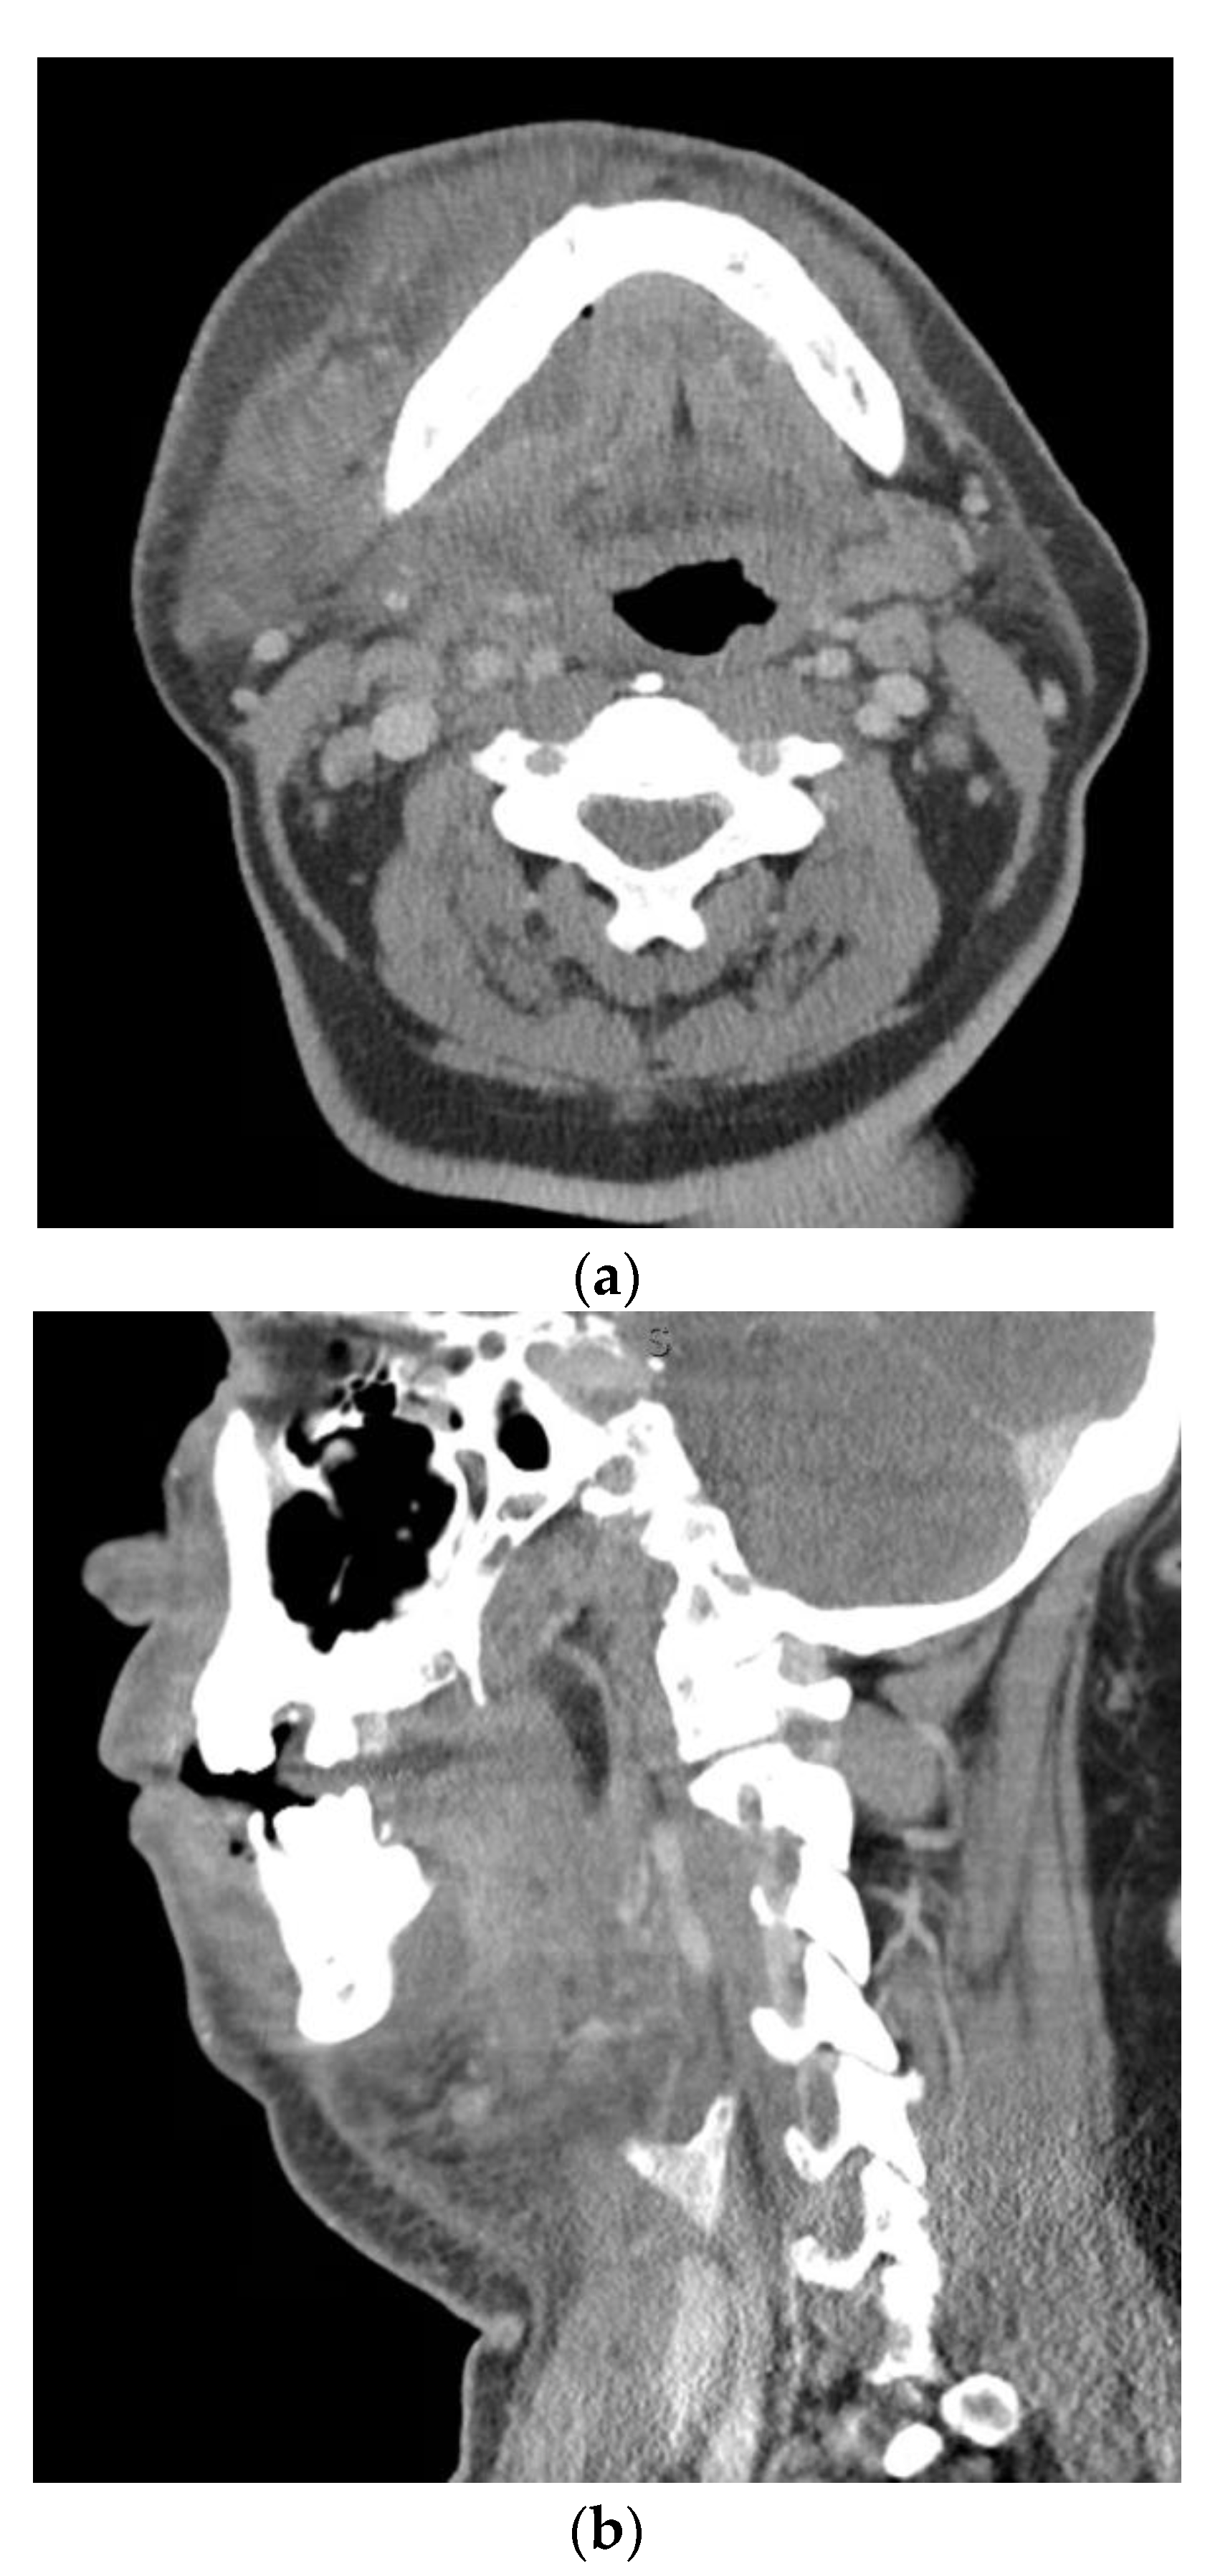

Severe odontogenic infection with progression to sepsis is rare. Given the sepsis definition update by the Sepsis-3 guidelines in 2016, it is highly unlikely a severe odontogenic infection would lead to sepsis in the absence of other complications discussed elsewhere in this article. However, bacteremia, defined as the presence of microorganisms in the blood by blood culture, may be more common Figure 3. In a study by Weise et al. of 483 patients with severe odontogenic infections, 3.3% of the study population showed a septic course. It is important to note that the criteria used to define sepsis is not described in this study. From the results, it seems the authors used the systemic inflammatory response syndrome (SIRS) criteria []. This criteria, as detailed by the Sepsis-3 guidelines, is useful in the general diagnosis of infection. With this in mind, the percentage of patients with septic progression from severe odontogenic infections is likely much lower. Reported risk factors that may promote septic progression in patients with severe odontogenic infections include frailty, immunosuppression, children under one year of age, adults over 75 years of age, and drug users []. Early detection and timely treatment of sepsis from any cause increases the likelihood of survival [].

Figure 3.

Axial (a) and sagittal (b) computed tomography scan views of a patient with a left parapharyngeal space infection with significant gas formation. Air and fluid extended within the retropharyngeal space to the level of C6/7. Bacteremia was present, with blood cultures positive for Streptococcus anginosus.